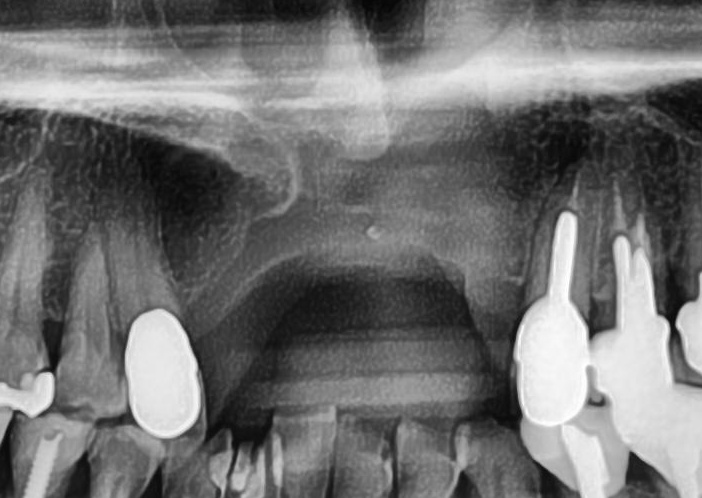

今回の患者様はインプラント植立を希望され、右上1番目・2番目、左上1番目・2番目の合計4本の植立が決まりました。

しっかりとインプラント埋め込まれた後は、動揺がないか、噛んだ時に当たらないかなどを確認して、最後にパノラマ写真を撮影して今回のオペは終了となりました。